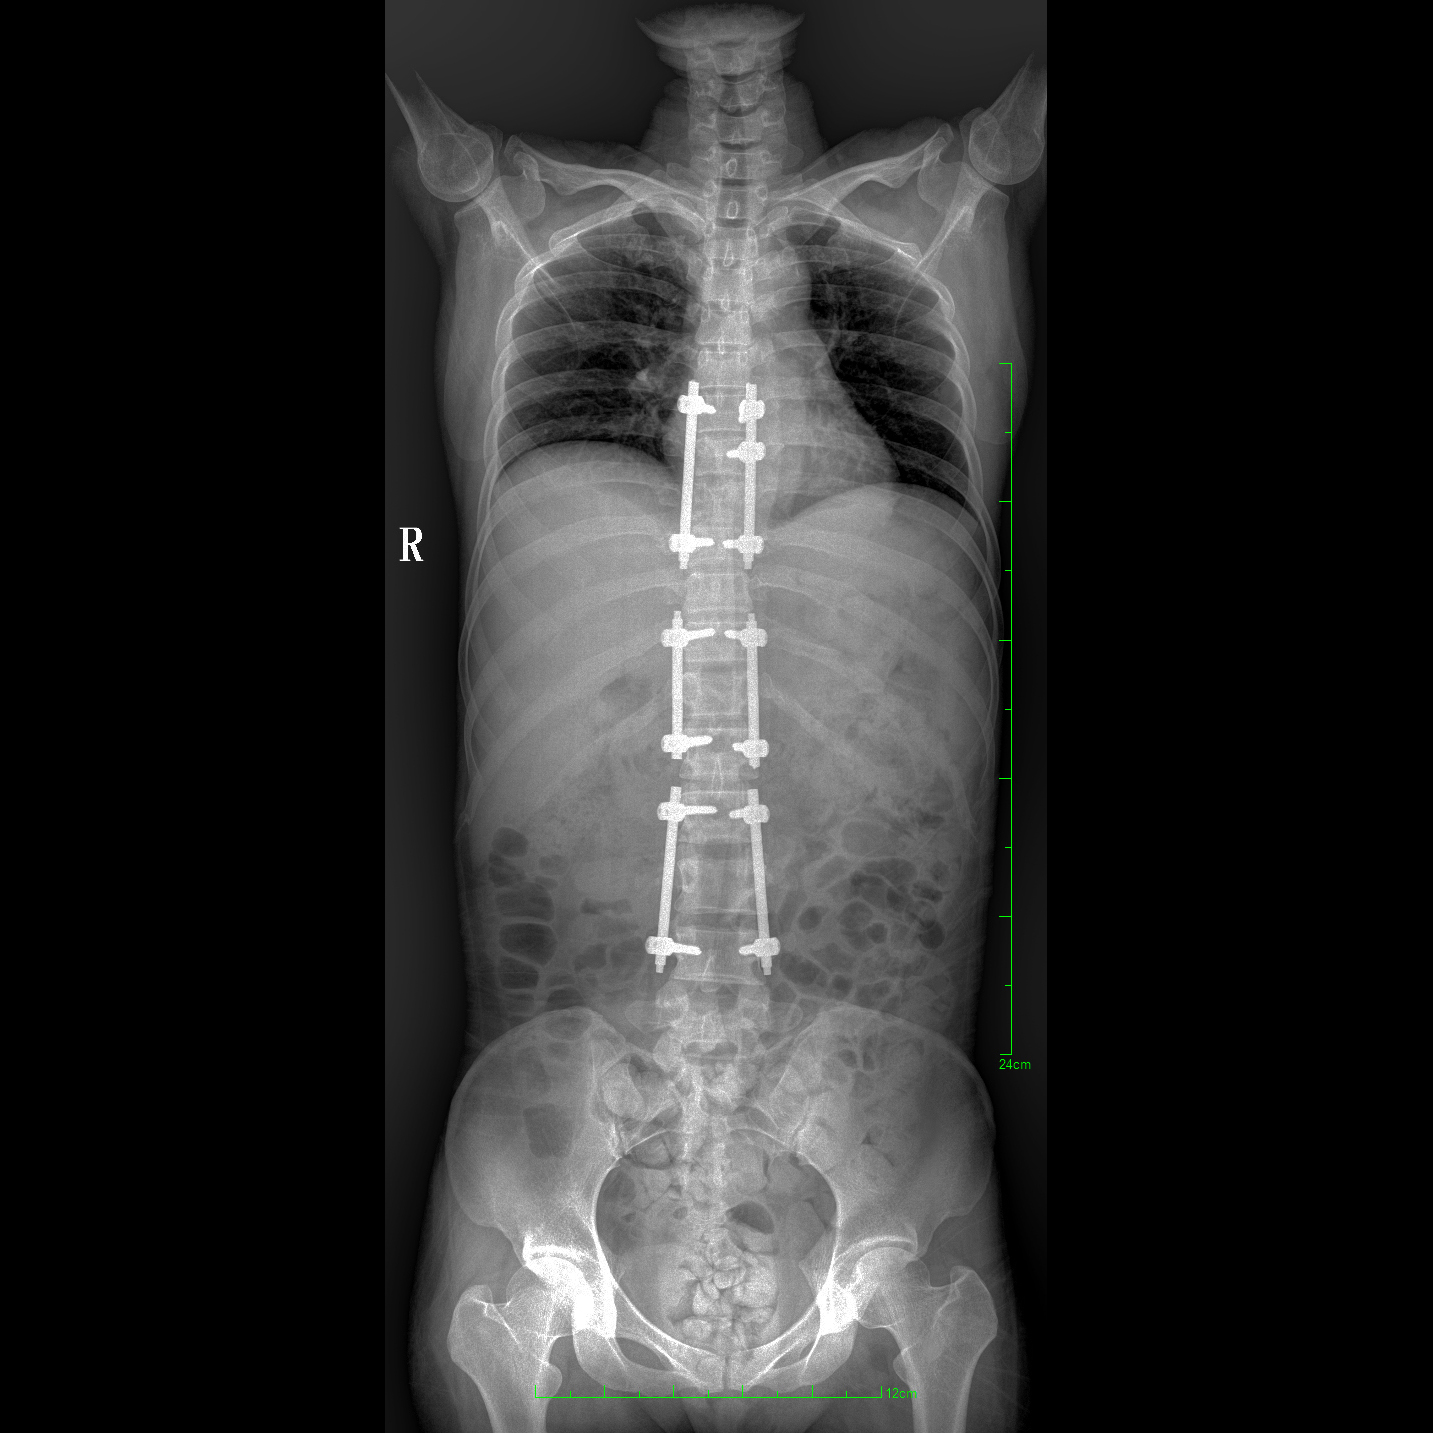

支持全脊柱攝影、雙下肢攝影、脊髓造影、復(fù)雜創(chuàng)傷、人工關(guān)節(jié)置換、關(guān)節(jié)損傷的修復(fù)重建等大視野臨床應(yīng)用

17"*34"有效視野,一次成像不拼接。相較于多張攝影再軟件拼接的DR設(shè)備,PLX8600解決了拼接圖像存在密度不均勻,拼接處圖像配準(zhǔn)和放大效應(yīng)等問(wèn)題,給臨床帶來(lái)了大視野影像解決方案,可一次性覆蓋全脊柱或雙下肢影像。

除常規(guī)靜態(tài)攝影外,PLX8600大平板具備動(dòng)態(tài)透視和點(diǎn)片功能,透視采集功能可支持大視野、多角度的可視化觀察。通過(guò)可視化的動(dòng)態(tài)影像,配合點(diǎn)片功能,能夠很好的觀察復(fù)雜部位病灶,有效的抓取關(guān)鍵幀,降低患者多次攝片的概率。如:全脊柱狀態(tài)評(píng)估、長(zhǎng)骨關(guān)節(jié)活動(dòng)度、下肢靜脈造影瓣膜功能評(píng)估、消化道功能評(píng)估、脊髓造影等更多大視野臨床應(yīng)用。